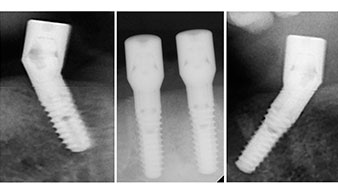

Zur Planung und Risikominimierung wurde eine dreidimensionale Volumentomografie (DVT, Planmeca) erstellt. Dieses zeigte, dass die Qualität und Quantität des Knochens für eine Operation und Sofortversorgung nach der Fast & Fixed-Methode ausreichend war. Nach Protokoll dieses Konzeptes wird in Regio 35, 32, 42 und 45 implantiert. Durch die bis zu 45-Grad-Schiefstellung der distalen Implantate wird das Durchtrittsprofil nach posterior verlegt und ein größeres Stützpolygon erreicht (Abb. 3).

Um die Divergenz der distalen Implantate auszugleichen, werden abgewinkelte Abutments (35 Grad) eingeschraubt, sodass die Austrittsprofile sämtlicher Implantate möglichst senkrecht zur Kauebene stehen. Dies ist Voraussetzung, um die provisorische und später auch die endgültige Versorgung okklusal verschrauben zu können (Abb. 15 und 16).

Nach der Zeit, die für die Osseointegration benötigt wird, kann die endgültige Abformung der Implantate erfolgen und entsprechend die endgültige Arbeit angefertigt werden (Abb. 19 und 20). Hier können Behandler und Patient gemeinsam entscheiden, ob diese eine Keramik- oder Kunststoffverblendung, ein Zirkon- oder Metallgerüst bekommen soll. Im vorliegenden Fall hat sich das Team um Dr. Pascu, aufgrund der unklaren Prognose der Oberkieferbezahnung und des elongierten Zahnes 24, für eine Kunststoffverblendung entschieden. Diese ist im Allgemeinen wesentlich einfacher umzustellen und der neuen Situation im Oberkiefer anzupassen.